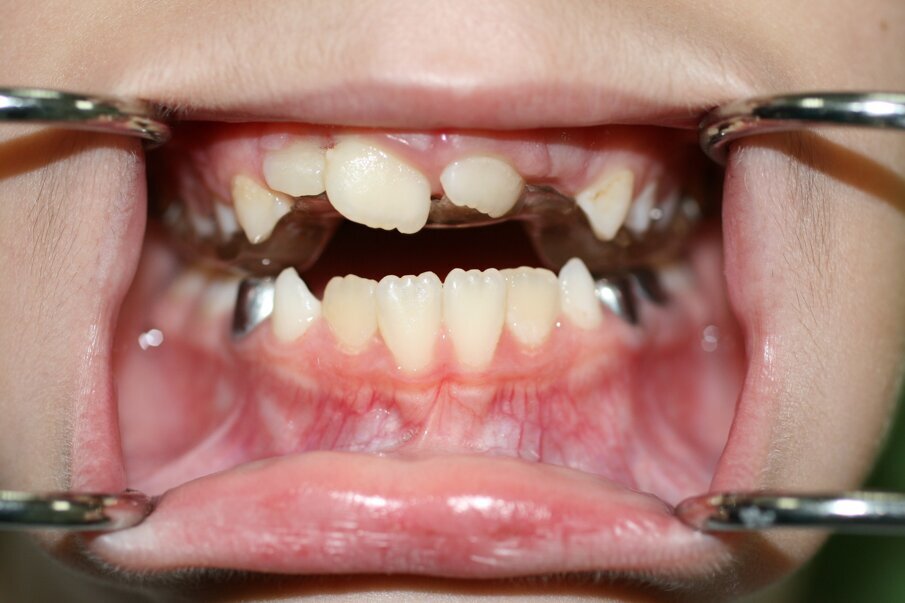

At one-week follow up, the patient was reviewed. She had no complaints. Tooth 21 had begun to erupt (Fig. 12). At one month’s follow up, tooth 21 had erupted in cross bite. Tooth 11 was already in cross bite.

Phase 3

• This phase included interceptive orthodontics which involved the cross bite correction of both teeth 11 & 21.

This would allow for spontaneous correction of the anterior cross bite of 21 due to the positive pressure of the patient’s tongue. At two-month follow up, tooth 21 had moved but was still in cross bite. We placed a composite ramp/restoration on 31 incisally, to finalise the correction of the cross bite. One month later, tooth 21 was over the bite and in the correct anterior-posterior position (Fig. 16 a & b).

Supernumerary teeth occur in 1.5-3.5% of cases in the permanent dentition8. Supernumeraries may present as tuberculate, conical, supplemental, inverted, pegged shaped or odontome shaped teeth. There is a male to female ratio approximately 2:1.8 They are more frequent in maxilla to mandible ratio around 5:1 and are called mesiodens in the maxillary anterior region. The effect of supernumeraries causing the failure or delayed eruption of permanent incisors was reported to be in 28% to 38% of the cases. Tuberculate supernumerary teeth are more likely to cause obstruction.9 In 54-78% of the cases removal of the supernumerary will result in the permanent incisor erupting spontaneously within an average of 16 months10. In this case, the inverted conical supernumerary was obstructing the eruption of 21, and its removal facilitated the eruption of 21 almost immediately. Correction of anterior crossbites is essential because they (if left untreated) may cause attrition to the labial surface of the upper incisors, fractures or mobility of incisor teeth or gingival recession. The treatment modalities adopted here fit with the best current practice UK guidelines.1,11